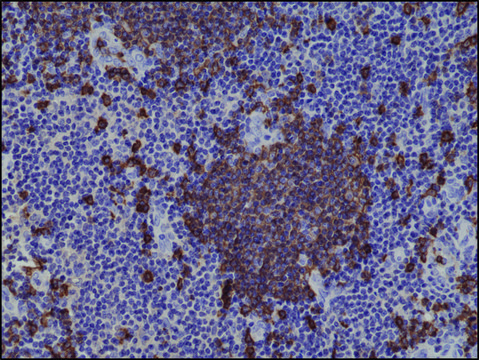

Anti-CD20 antibody, Rabbit monoclonal recombinant, expressed in HEK 293 cells, clone RM272, purified immunoglobulin